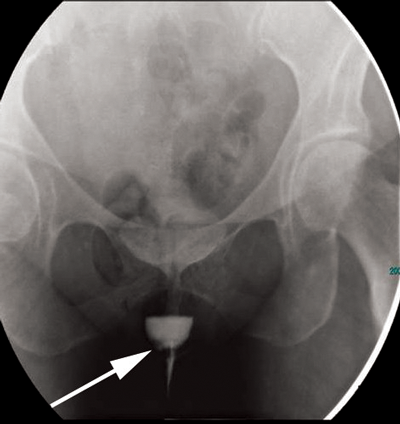

Figure 1a: Erect image taken from a voiding cystourethrogram

showing a urethral diverticulum with a filling defect (arrow).

Figure 1 shows a well defined rounded area filled with contrast that remains after bladder emptying. Note the small filling defect on the right side of the diverticulum (arrow), in keeping with a tumour. Double-balloon urethrography can also be used, despite having a greater sensitivity than voiding cystourethrography [2] it is more technically difficult. More recently, cross-sectional imaging has become more popular due to the greater need to delineate the diverticula and investigate malignant transformation [4].